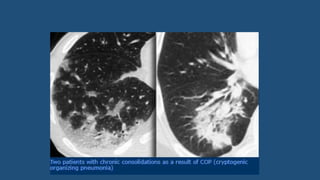

• Organizing pneumonia (OP)

• Represents an inflammatory process in which the healing process is

characterized by organization and cicatrization of the exudate rather than

by resolution and resorption.

• Aka 'unresolved pneumonia'.

• If no cause can be identified it is called cryptogenic organizing pneumonia

(COP).

• It was described in earlier years as Bronchiolitis-obliterans-organizing

pneumonia (BOOP).